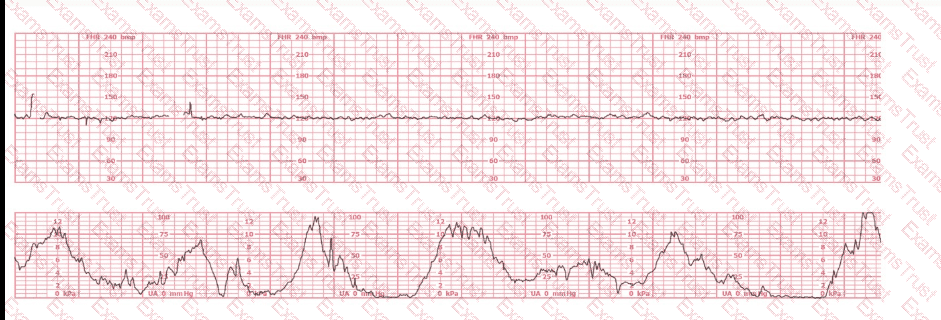

A woman (G1P0) arrives in triage with a pain score of 4/10 at 39-weeks gestation. The fetal heart rate tracing shown is obtained. The best intervention is to:

The tracing shown is a:

Based on the tracing shown, the first action should be to